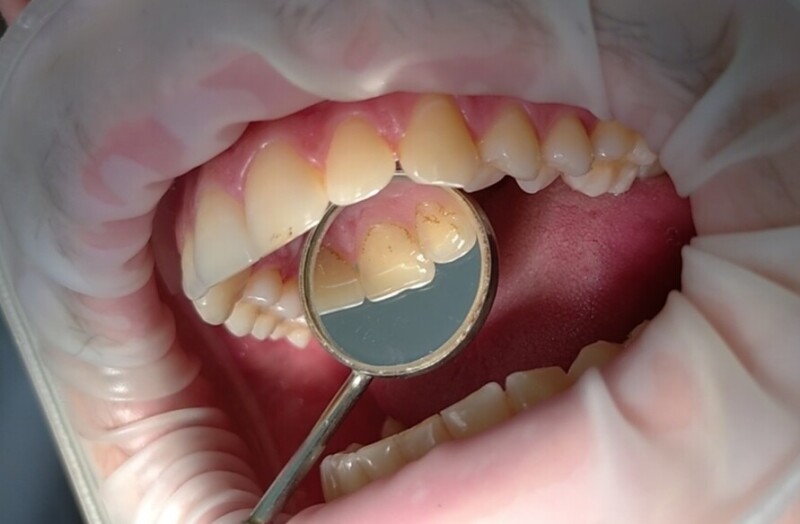

Професійна гігієна порожнини рота – це комплекс заходів, які забезпечують видалення зубного каменю і нальоту на зубах та язику.

- зняття зубних каменів ультразвуковим скелером;

- чищення м’якого нальоту методом Air-Flow;

- полірування та шліфування зубів абразивною пастою.